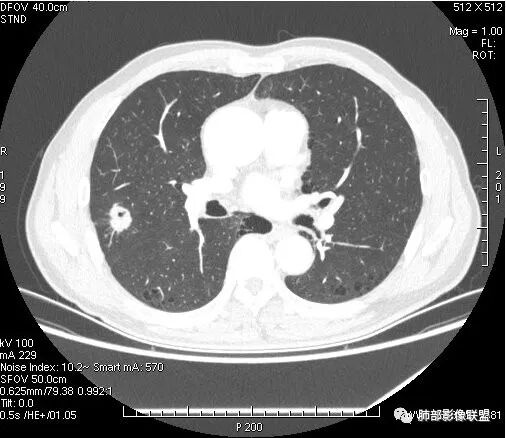

影像学改变:

1.右肺上叶后段类圆形结节影,密度不均,有坏死空洞,坏死比较彻底,内外壁都较清楚。

2.病灶有浅切迹,没有深分叶,毛刺大多细长且柔软。

3.可见棘状突起及胸膜牵拉,但未见胸膜凹陷。

什么意思?结节影有牵拉的动作,但似乎“出工不出力”,收缩力羸弱!

4.病灶轻到中度强化。病灶内血管走行较完好,病灶旁血管局部显示粗大。

5.支气管关系不确定。

6.灶周见小结节影(卫星灶),边界不甚清晰。